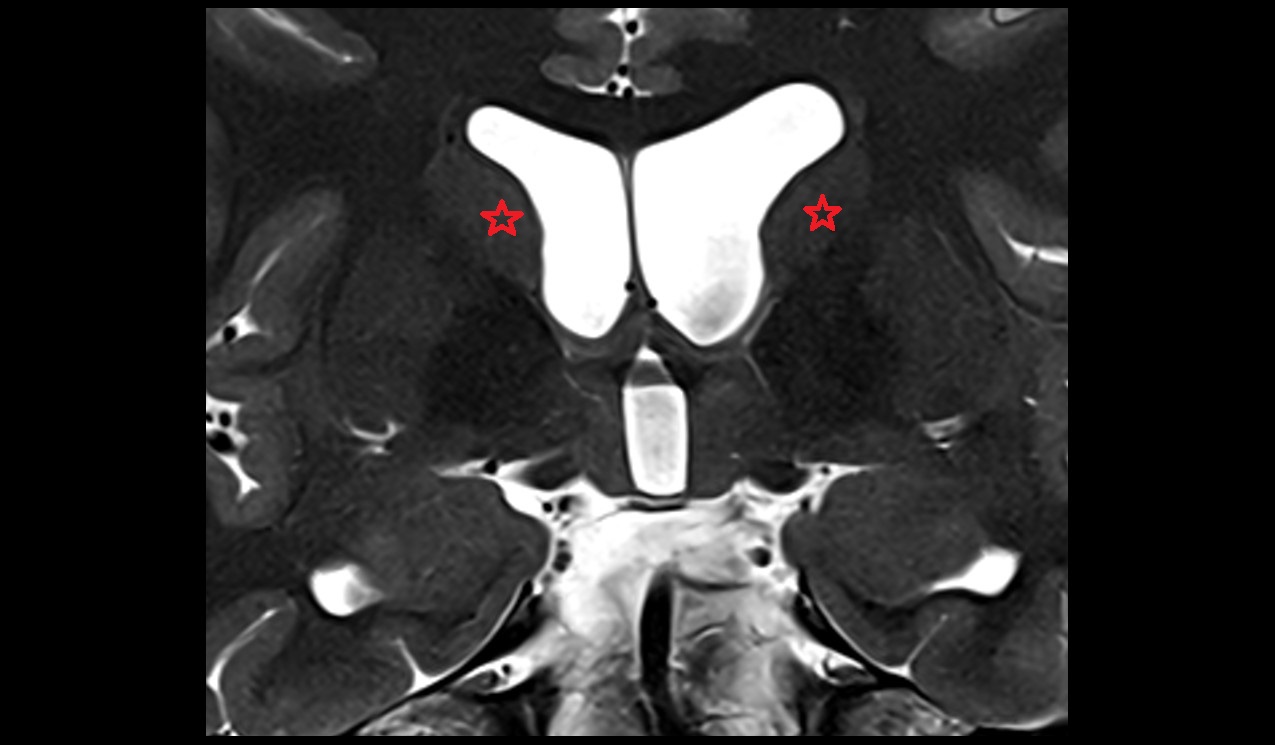

- Central part of lateral ventricle

- Frontal horn of lateral ventricle

- Occipital horn of lateral ventricle

- Temporal horn of lateral ventricle